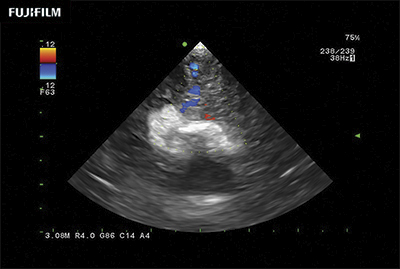

Liver Spectral Doppler using C22I

Curved array deep penetration “I” style finger-grip transducer for open kidney surgical procedures. Allows for palpating organs and scanning at the same time.